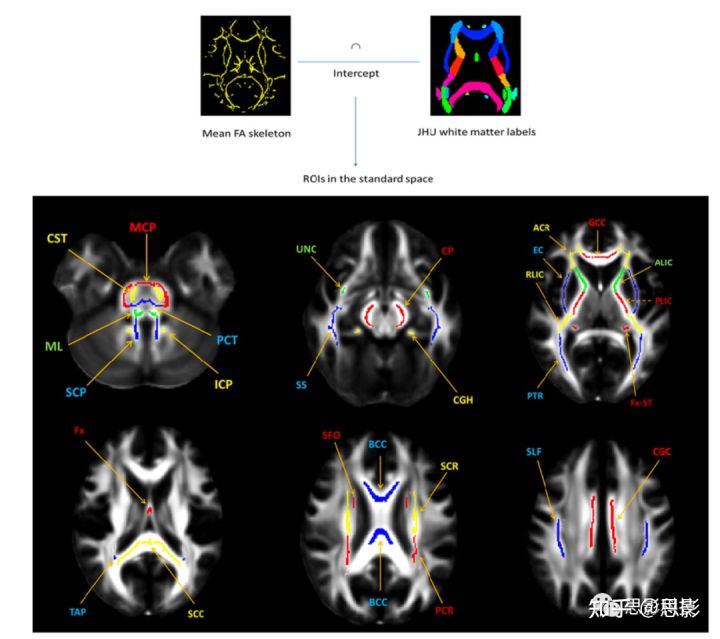

研究白质微观结构变化的另一种方法是q空间成像。q空间方法使用了扩散加权q空间信号与扩散位移分布空间之间的傅里叶关系。这与MRI中k空间与图像空间的关系类似。水的扩散函数,概率密度函数(PDF)又称为平均表观传播器(MAP)或集合平均传播器(EAP),可以通过q空间成像公式来估计。PDF和q空间扩散信号有傅里叶变换关系:

q-Space成像指标

所有5个HYDI shell数据都被用于q空间成像分析。给出q空间扩散信号的傅里叶关系和扩散概率密度函数,P0是由q空间信号的体积积分估计得到的(中心坐标定理):